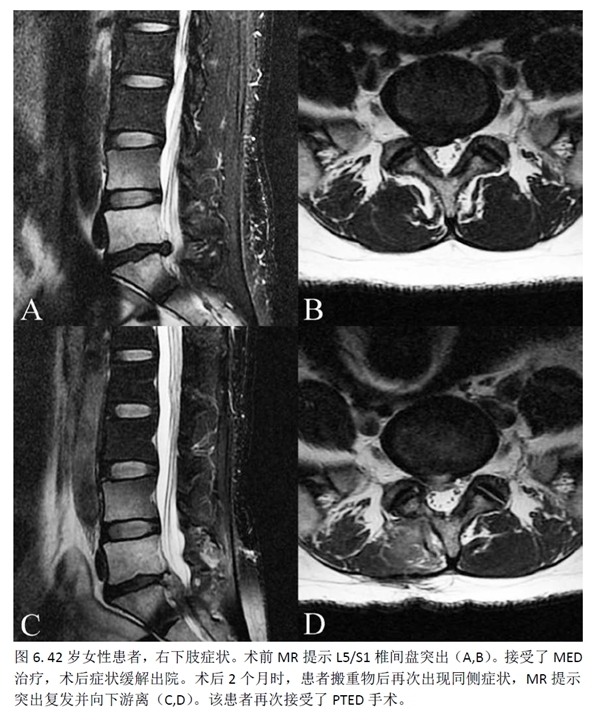

此外,2例(2.5%)PTED组患者及7例(9.59%)MED组患者出现新发患肢麻木感,但两组间没有统计学差异。MED组还有1例(1.36%)患者发生伤口愈合不良。PTED组有5例(6.25%)患者因复发/残留而需进行再次手术,MED组则为3例(4.11%)。再次手术率方面,两组之间没有统计学差异(p=0.818)。